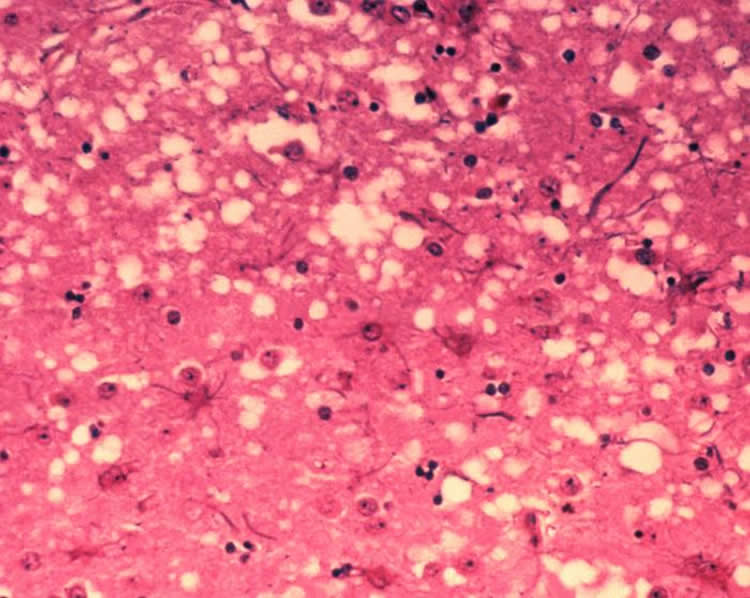

Prions are abnormal, transmissible pathogenic agents that induce abnormal folding of specific, normal cellular proteins. Because these proteins are concentrated in brain tissue, brain damage is characteristic of prion diseases. Prion diseases generally progress rapidly and are associated with high mortality. Prion disease occurs when the normal cellular form of prion-related protein converts or conformationally changes to the disease form. Once the disease form is introduced, it becomes self-perpetuating as it converts the normal form into more of the disease form. CWD is currently spreading throughout the U.S. and Canada, is also present in South Korea, and was just diagnosed in a first reindeer in Norway.

Image Credit: Image is credited to Dr. Al Jenny and is in the public domain.